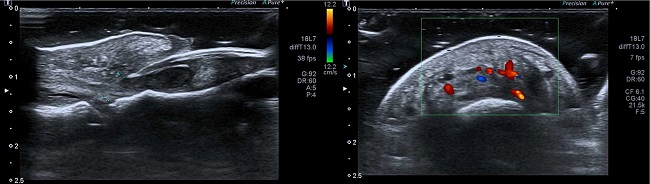

Ultrasonography showed significant thickening of the proximal nail fold and a hypoechoic halo around the nail matrix, associated with disruption of the proximal portion of the ventral nail plate, suggestive of a fragment. No bone remodeling was identified. The Doppler revealed an increase in flow near the proximal nail fold and matrix (Figure 3).

In this regard, Fernández et al. established diagnostic ultrasound criteria for retronychia: the presence of a hypoechoic halo or band around the origin; distance between the nail plate origin and the distal phalanx base (≥5.1 mm in the hallux and/ or difference ≥0.5 mm regarding the contralateral hallux); proximal nail fold thickness (≥2.2 mm for men or ≥1.9 mm for women and/or ≥0.3 mm concerning the contralateral hallux). Thus, the simultaneous presence of three criteria may indicate the diagnosis of unilateral retronychia, and, in bilateral cases, the presence of at least two criteria, one of which is the presence of a hypoechoic halo, may favor the diagnosis.10

In the case reported here, ultrasonography demonstrates the three diagnostic ultrasonographic criteria (increased distance between the nail plate origin and the distal phalanx base; increased proximal nail fold thickness, and a hypoechoic halo below the origin of the plaque).There is also a growth in blood flow in the dermis of the nail fold posterior to Doppler.